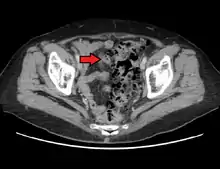

Imaging

- Contrast CT is the investigation of choice in acute episodes of diverticulitis and where complications exist.